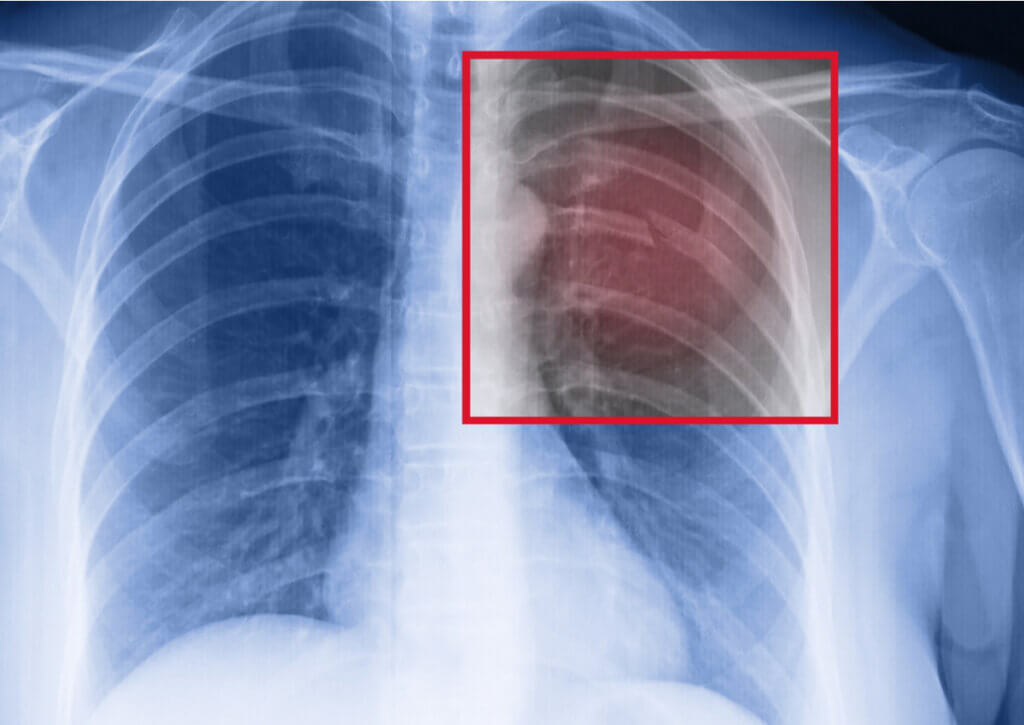

Si eres deportista y sufres una fractura costal por estrés, lo primero será consultar con un médico. Te realizarán una radiografía del tórax para corroborar la lesión y se evaluará su extensión.